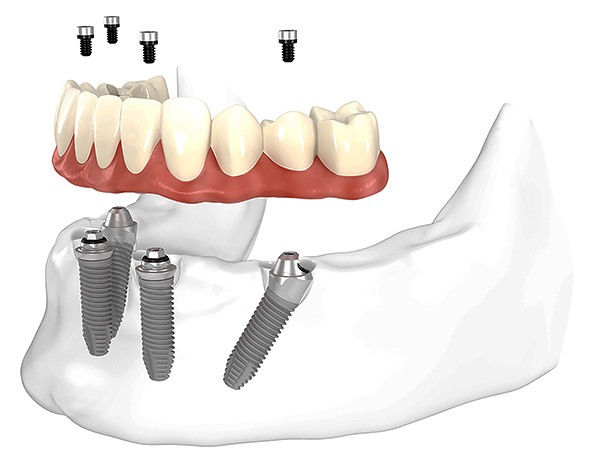

Entre as tecnologias de carregamento imediato, vários protocolos principais podem ser distinguidos: próteses em quatro implantes (all-on-4 - patenteados pela Nobel), em seis implantes (all-on-6) e o próprio método basal.

Em todos os casos, são utilizados implantes instalados precisamente nas camadas profundas do tecido ósseo (existem muitos modelos e variedades desses implantes). Eles estão ligados não apenas na zona alveolar, mas também na seção basal, a membrana cortical do osso. E com atrofia aguda, os ossos e contrafortes zigomáticos (linhas de força) do crânio também são usados. O grau de fixação de tais implantes é várias vezes maior e atinge 100 Newtons versus implantes clássicos, com um índice de 30 a 45 Newtons.